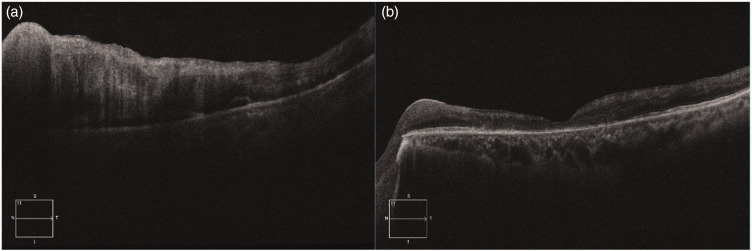

本病例报告一例罕见的继发于视网膜中央静脉阻塞的新生血管性青光眼,患者为30岁出头的健康男性,表现为急性单侧视力丧失、眼痛和眼压升高。眼科成像,包括超宽视场眼底摄影和光学相干断层扫描,显示视网膜出血、视网膜内积液和虹膜新生血管形成,与缺血性视网膜中央静脉闭塞和继发性新生血管性青光眼一致。值得注意的是,系统评估显示严重的高脂血症与患者严格的非素食饮食有关,没有其他可识别的危险因素。治疗包括玻璃体内注射抗血管内皮生长因子,Ahmed青光眼瓣膜植入术,全视网膜光凝术后玻璃体切除。患者在开始降脂治疗和饮食咨询后,视力部分恢复。本病例强调了考虑可改变的代谢因素的重要性,特别是极端的饮食模式,在年轻的视网膜中央静脉闭塞患者。它支持将全身脂质筛查和饮食评估纳入非典型视网膜血管事件的诊断工作。虽然不能确定因果关系,但本病例提倡进一步研究饮食相关高脂血症在眼部血管疾病中的全身性影响。

This case report presents a rare instance of neovascular glaucoma secondary to central retinal vein occlusion in a previously healthy man in his early 30s who exhibited acute unilateral vision loss, ocular pain, and elevated intraocular pressure. Ophthalmic imaging, including ultra-widefield fundus photography and optical coherence tomography, revealed retinal hemorrhages, intraretinal fluid, and iris neovascularization consistent with ischemic central retinal vein occlusion and secondary neovascular glaucoma. Notably, systemic evaluation revealed severe hyperlipidemia associated with the patient's strict nonvegetarian diet, with no other identifiable risk factors. Treatment included intravitreal antivascular endothelial growth factor injections, Ahmed glaucoma valve implantation, and panretinal photocoagulation followed by pars plana vitrectomy. The patient experienced partial visual recovery after the initiation of lipid-lowering therapy and dietary counseling. This case underscores the importance of considering modifiable metabolic factors, particularly extreme dietary patterns, in young patients presenting with central retinal vein occlusion. It supports the incorporation of systemic lipid screening and dietary assessment into the diagnostic workup of atypical retinal vascular events. Although causality cannot be established, this case advocates the need for further investigation into the systemic implications of diet-related hyperlipidemia in ocular vascular disease.